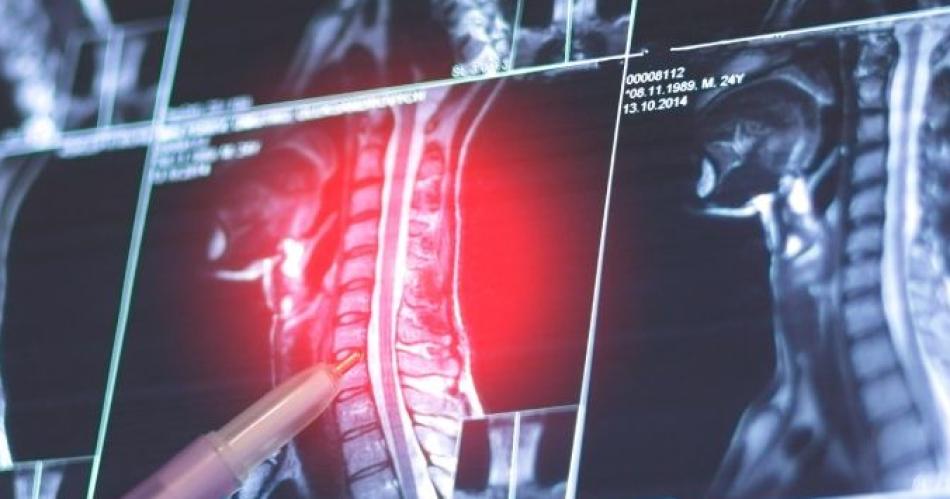

Para diagnosticar los osteoblastomas, los especialistas realizan radiografías y otras pruebas de diagnóstico por imagen como tomografía computarizada (TC) y resonancia magnética nuclear (RMN). "Para confirmar el diagnóstico de osteoblastoma, además, se toma una muestra de tejido y lo examina al microscopio (biopsia)", señalaron los expertos.